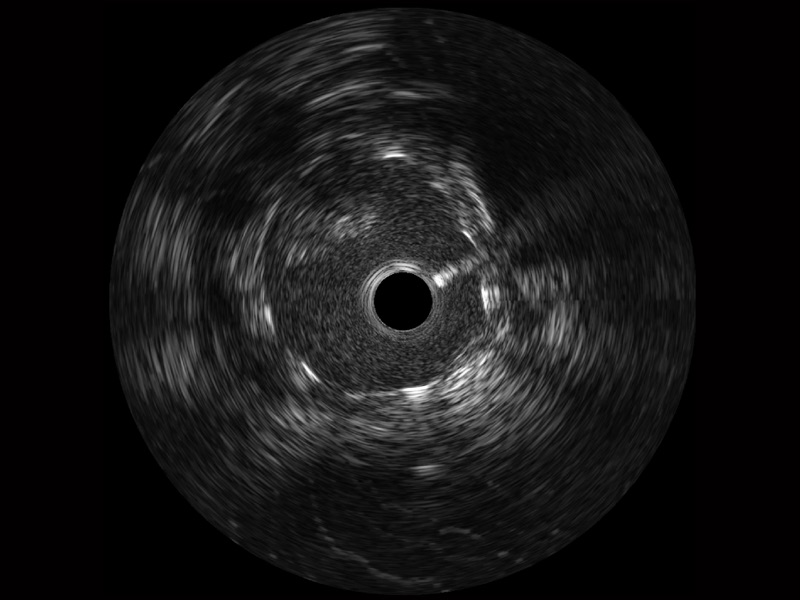

db真人体育官网宽频IVUS图像

传统IVUS图像

对比传统IVUS导管成像,db真人体育官网宽频IVUS图像的近场支架梁显影更细腻,远场中膜外血管仍清晰可辨,兼顾远中近,兼顾分辨力与穿透深度